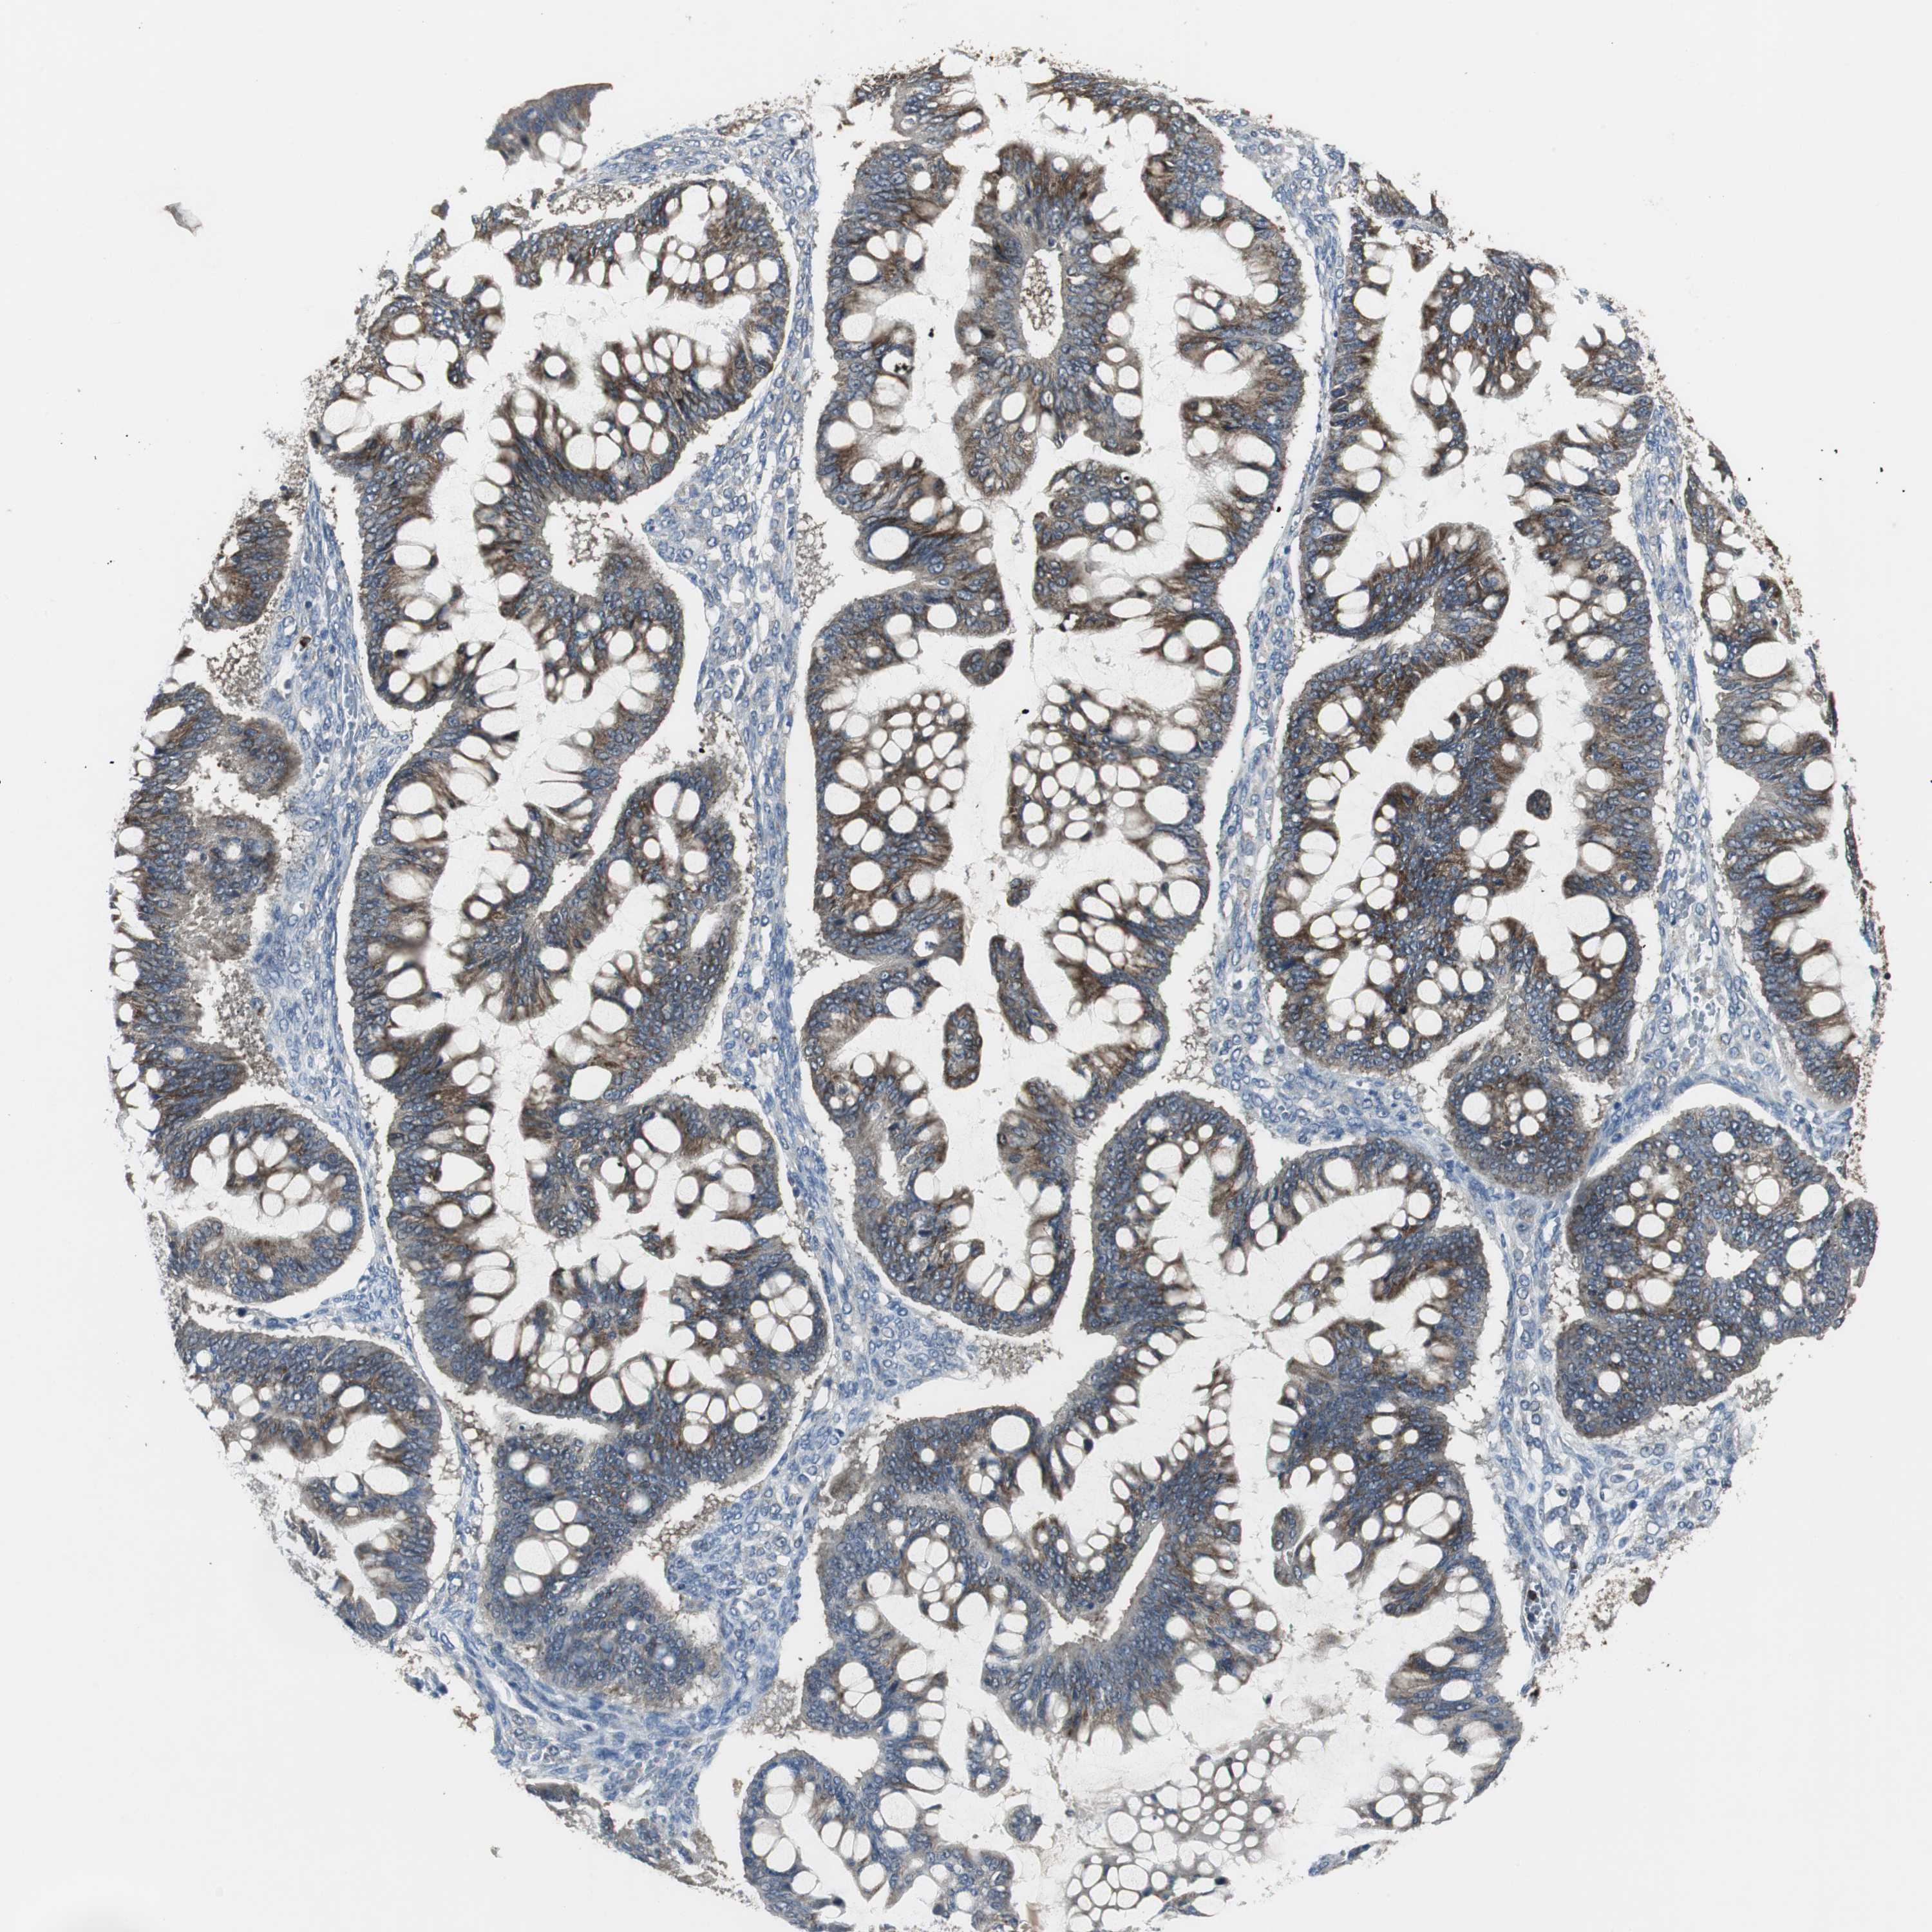

OVARIAN CANCER - Protein expressioni

A mouse-over function shows sample information and annotation data. Click on an image to view it in a full screen mode. Samples can be filtered based on level of antibody staining by selecting one or several of the following categories: high, medium, low and not detected. The assay and annotation is described here.

Note that samples used for immunohistochemistry by the Human Protein Atlas do not correspond to samples in the TCGA dataset.

Antibody stainingi

Antibody staining in the annotated cell types in the current human tissue is reported as not detected, low, medium, or high, based on conventional immunohistochemistry profiling in selected tissues. This score is based on the combination of the staining intensity and fraction of stained cells.

Each image is clickable and will lead to virtual microscopy that enables deeper exploration of all samples and also displays staining intensity scores, fraction scores and subcellular localization as well as patient and tissue information for each sample.

Antibody HPA006514

Carcinoma, endometroid

Carcinoma, NOS